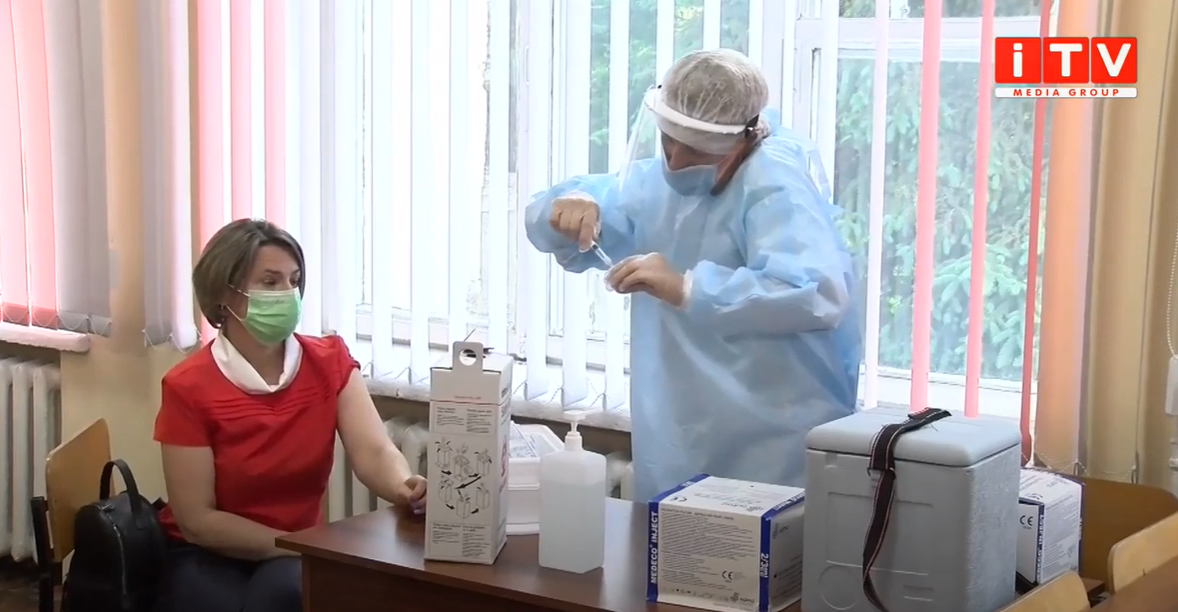

Коронавірус повертається: як стрімко зростає кількість хворих на Рівненщині (ВІДЕО)